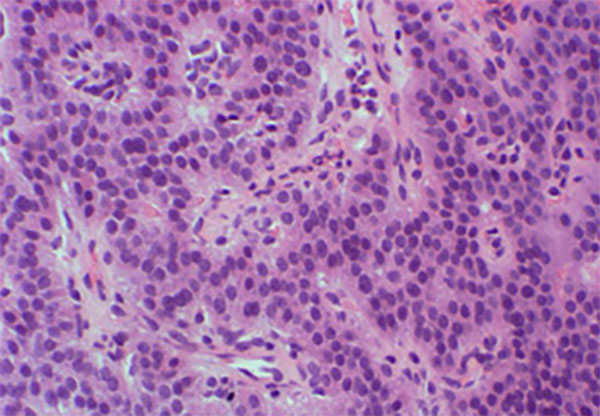

NETとNECの病理組織像の違い

膵NET

比較的均一な円形の核を有する腫瘍細胞が規則正しく配列、増殖しています。

笹野先生よりご提供